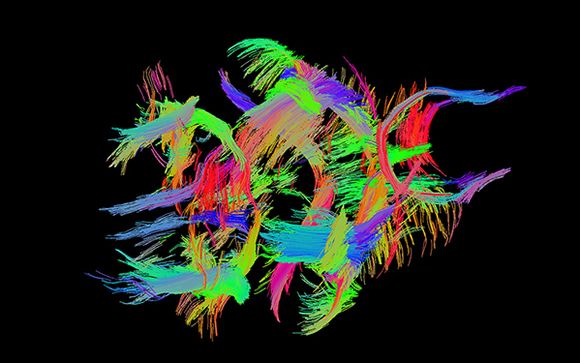

Los resultados del estudio, publicado en Journal of Cerebral Blood Flow & Metabolism, revelaron mejorías significativas en los ratones tratados con IL-1Ra. “Registraron una reducción del volumen de infarto (medido mediante técnicas de neuroimagen y con histología post mortem), una reducción de la rotura de la barrera hematoencefálica, habitual cuando ocurre un ictus, y una mejoría en cuanto a los déficits sensoriomotores causados por la isquemia”, explica Pradillo.